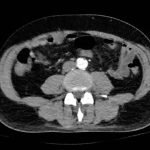

Chest x-ray and CT angiogram was performed to evaluate his thoracic and abdominal vasculature. Chest x-ray did not show any significant widening of the mediastinum. The CT angiogram demonstrated an intimal tear along the aortic arch separating a true and false aortic lumen, consistent with an acute aortic dissection. The true lumen (highlighted in blue in images 1-5) can be identified by continuity with an undissected part of the aorta1. While the false lumen (highlighted in red in images 1-5) can be identified by its crescent shape and larger cross-sectional area.1